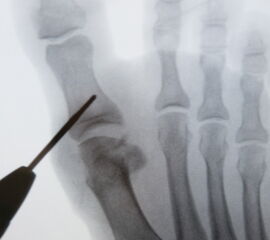

• Belastete Röntgenaufnahmen im Stehen in 2 oder 3 Ebenen.

• Je nach OP entsprechende Planung der Osteotomie anhand der Röntgenbilder.